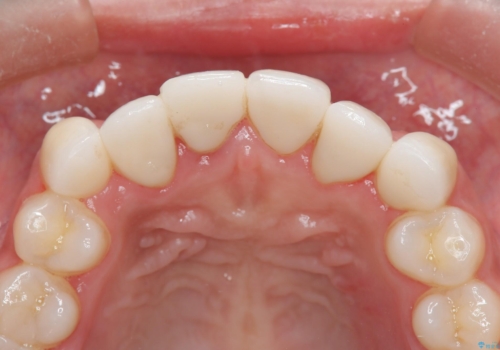

歯肉の治りを待ったうえで(約8か月)、最終補綴することとなりました。

補綴はスペシャルです。

結果的に期間がかなりかかってしまいましたが、患者様に満足していただける結果となりました。